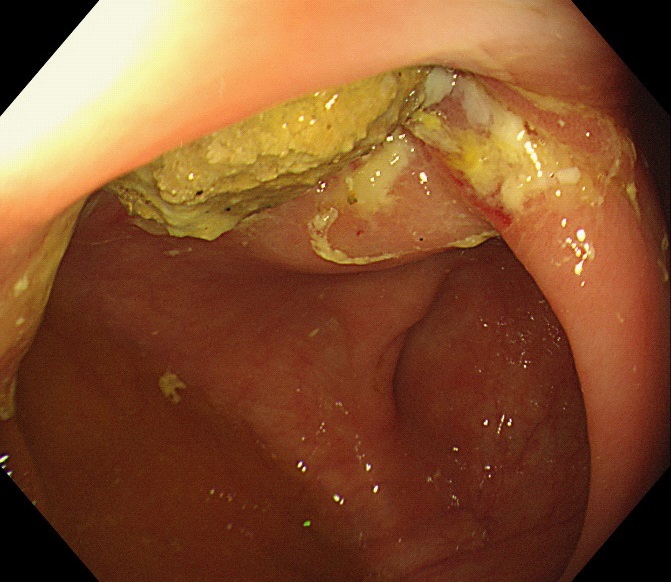

Figure 4: The internal mucosa of the diverticulum was hyperemia, and no perforation was observed after the fecalith was removed.

The computed tomography scan of abdomen showed about 20 mm X 20 mm circular high density shadow in right colon, which can be observed in colonic lumen but protruding out of the lumen. Colonoscopy (Figure 3) was also performed and the fecal impaction was identified in the cecal diverticulum above the ileocecal valve. The mucosa surrounding the diverticulum was hyperemic and edema. Than the fecalith was removed successfully with a foreign forceps under colonoscopy. The internal mucosa of the diverticulum was hyperemia, and no perforation was observed (Figure 4). The patient’s abdominal pain were relieved after endoscopic treatment. To prevent recurrence of the disease, surgical removal of the diverticulum was recommended but the patient was hesitant. There was no recurrence of abdominal pain and fecal impaction during 10 months follow-up.